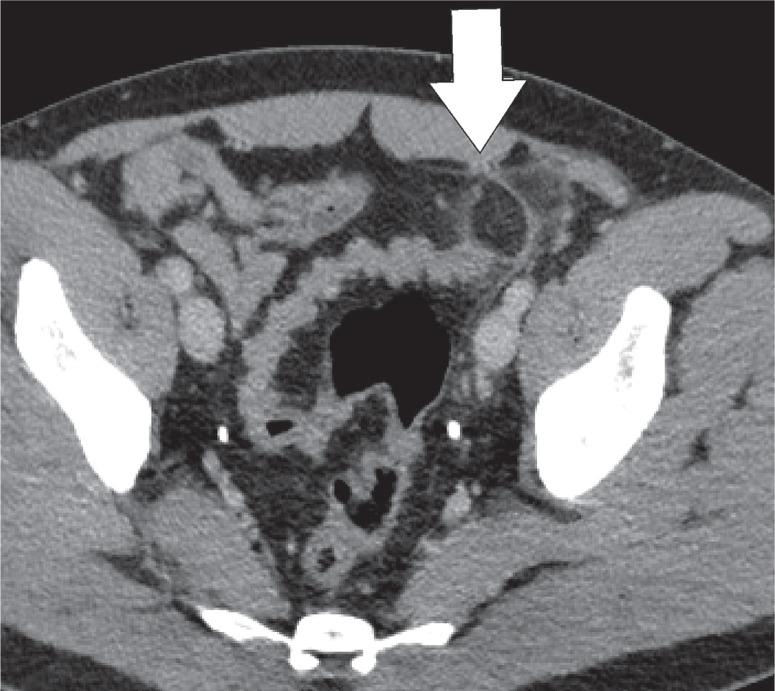

Intra-abdominal fat is abundantly present in both the peritoneum and retroperitoneum. Fat necrosis or inflammation are common findings in abdominal imaging. The most common pathologies that we encounter are epiploic appendagitis, omental infarction, mesenteric panniculitis, and encapsulated fat necrosis. Less common entities that can occur are pancreatic saponification, heterotopic mesenteric ossification, and pseudolipoma of the capsule of Glisson. These entities can mimic more urgent pathologies such as appendicitis, diverticulitis, or malignancies.

腹腔内脂肪大量存在于腹膜和腹膜后间隙。脂肪坏死或炎症是腹部影像学检查中的常见表现。我们遇到的最常见病理情况是网膜附件炎、网膜梗死、肠系膜脂膜炎和包裹性脂肪坏死。较少见的情况包括胰腺皂化、异位肠系膜骨化和肝门Glisson囊假脂肪瘤。这些病变可能会模仿更紧急的病理情况,如阑尾炎、憩室炎或恶性肿瘤。